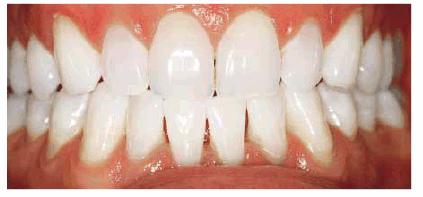

of this textbook. Typically, bleaching with 10% carbamide peroxide in a

custom-fitted tray easily treats discolorations due to aging, smoking, or

chromogenic foods, and beverages (Figures 16-16A 16-16B 16-17A, and 16-17B). Although these types of stains

generally require only 2 to 6 weeks of bleaching treatment, some are more

Figure 16-16A: Some teeth darken over time from chromagenic foods. Some patients' teeth are just naturally yellow.

Figure 16-16B: Whitening of the maxillary teeth using 10% carbamide peroxide in a custom tray results in a more pleasing smile. This patient is now interested in closing the spaces.

Figure 16-17A: Some teeth darken through natural aging.

Figure 16-17B: Whitening of the maxillary teeth using 10% carbamide peroxide in a custom tray produces a normal progression of color from gingival to incisal edge but offers a more pleasing, younger look to the patient.